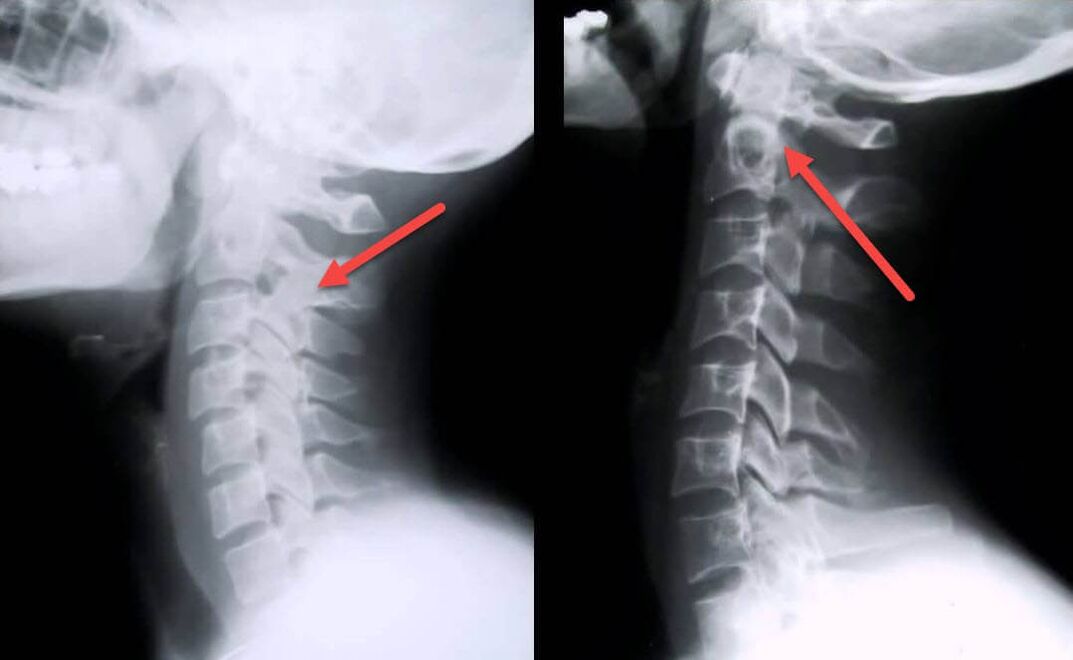

Diagnostiko-prozedurarik informatzaileena erradiografia da. 1. graduko patologiak 1. edo 2. etapa erradiologikoari dagozkio. Lortutako irudiek gaixotasunaren seinale tipikoak ikusten dituzte.

| 1. mailako osteokondrosi zerbikalaren X izpien faseak | Zeinu bereizgarriak |

|---|---|

| 1. etapa | Aldaketa txikiak bizkarrezurraren kurbaduran zerbikal eskualdean, segmentu bati edo gehiagori eragiten diote |

| 2. etapa | Orno arteko diskoen loditze arina, prozesu uncinateen deformazioa, lordosia zuzentzea, hezur-egituren hazkunde txikiak |